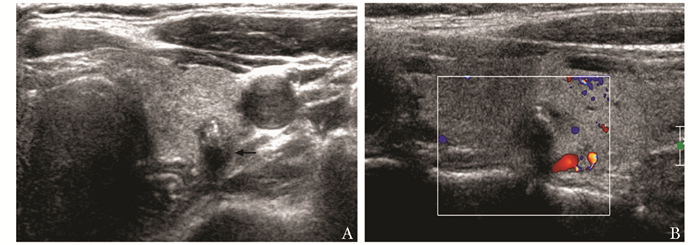

结果  在超声检查可疑恶性的162个甲状腺结节中, 经术后病理证实33个(20.37%)为良性, 其中以结节性甲状腺肿伴钙化或(和)纤维化最多见(12个, 36.36%)。误诊结节中最常见的超声征象为微小钙化(20个), 其他包括结节边界不规则(9个)、纵横比≥ 1(6个)、血流异常(6个)等。

Results  A total of 162 nodules were suspected malignant in ultrasonography, among which 33 (20.37%) were benign based on pathologic results, primarily nodular goiter with calcinosis/fibrosis(12, 36.36%). Microcalcification(20), irregular boundary of the nodules(9), a taller-than-wide shape(6), and abundant and abnormal blood flow(6) were the most common ultrasonographic signs in turn in those misdiagnosed nodules.